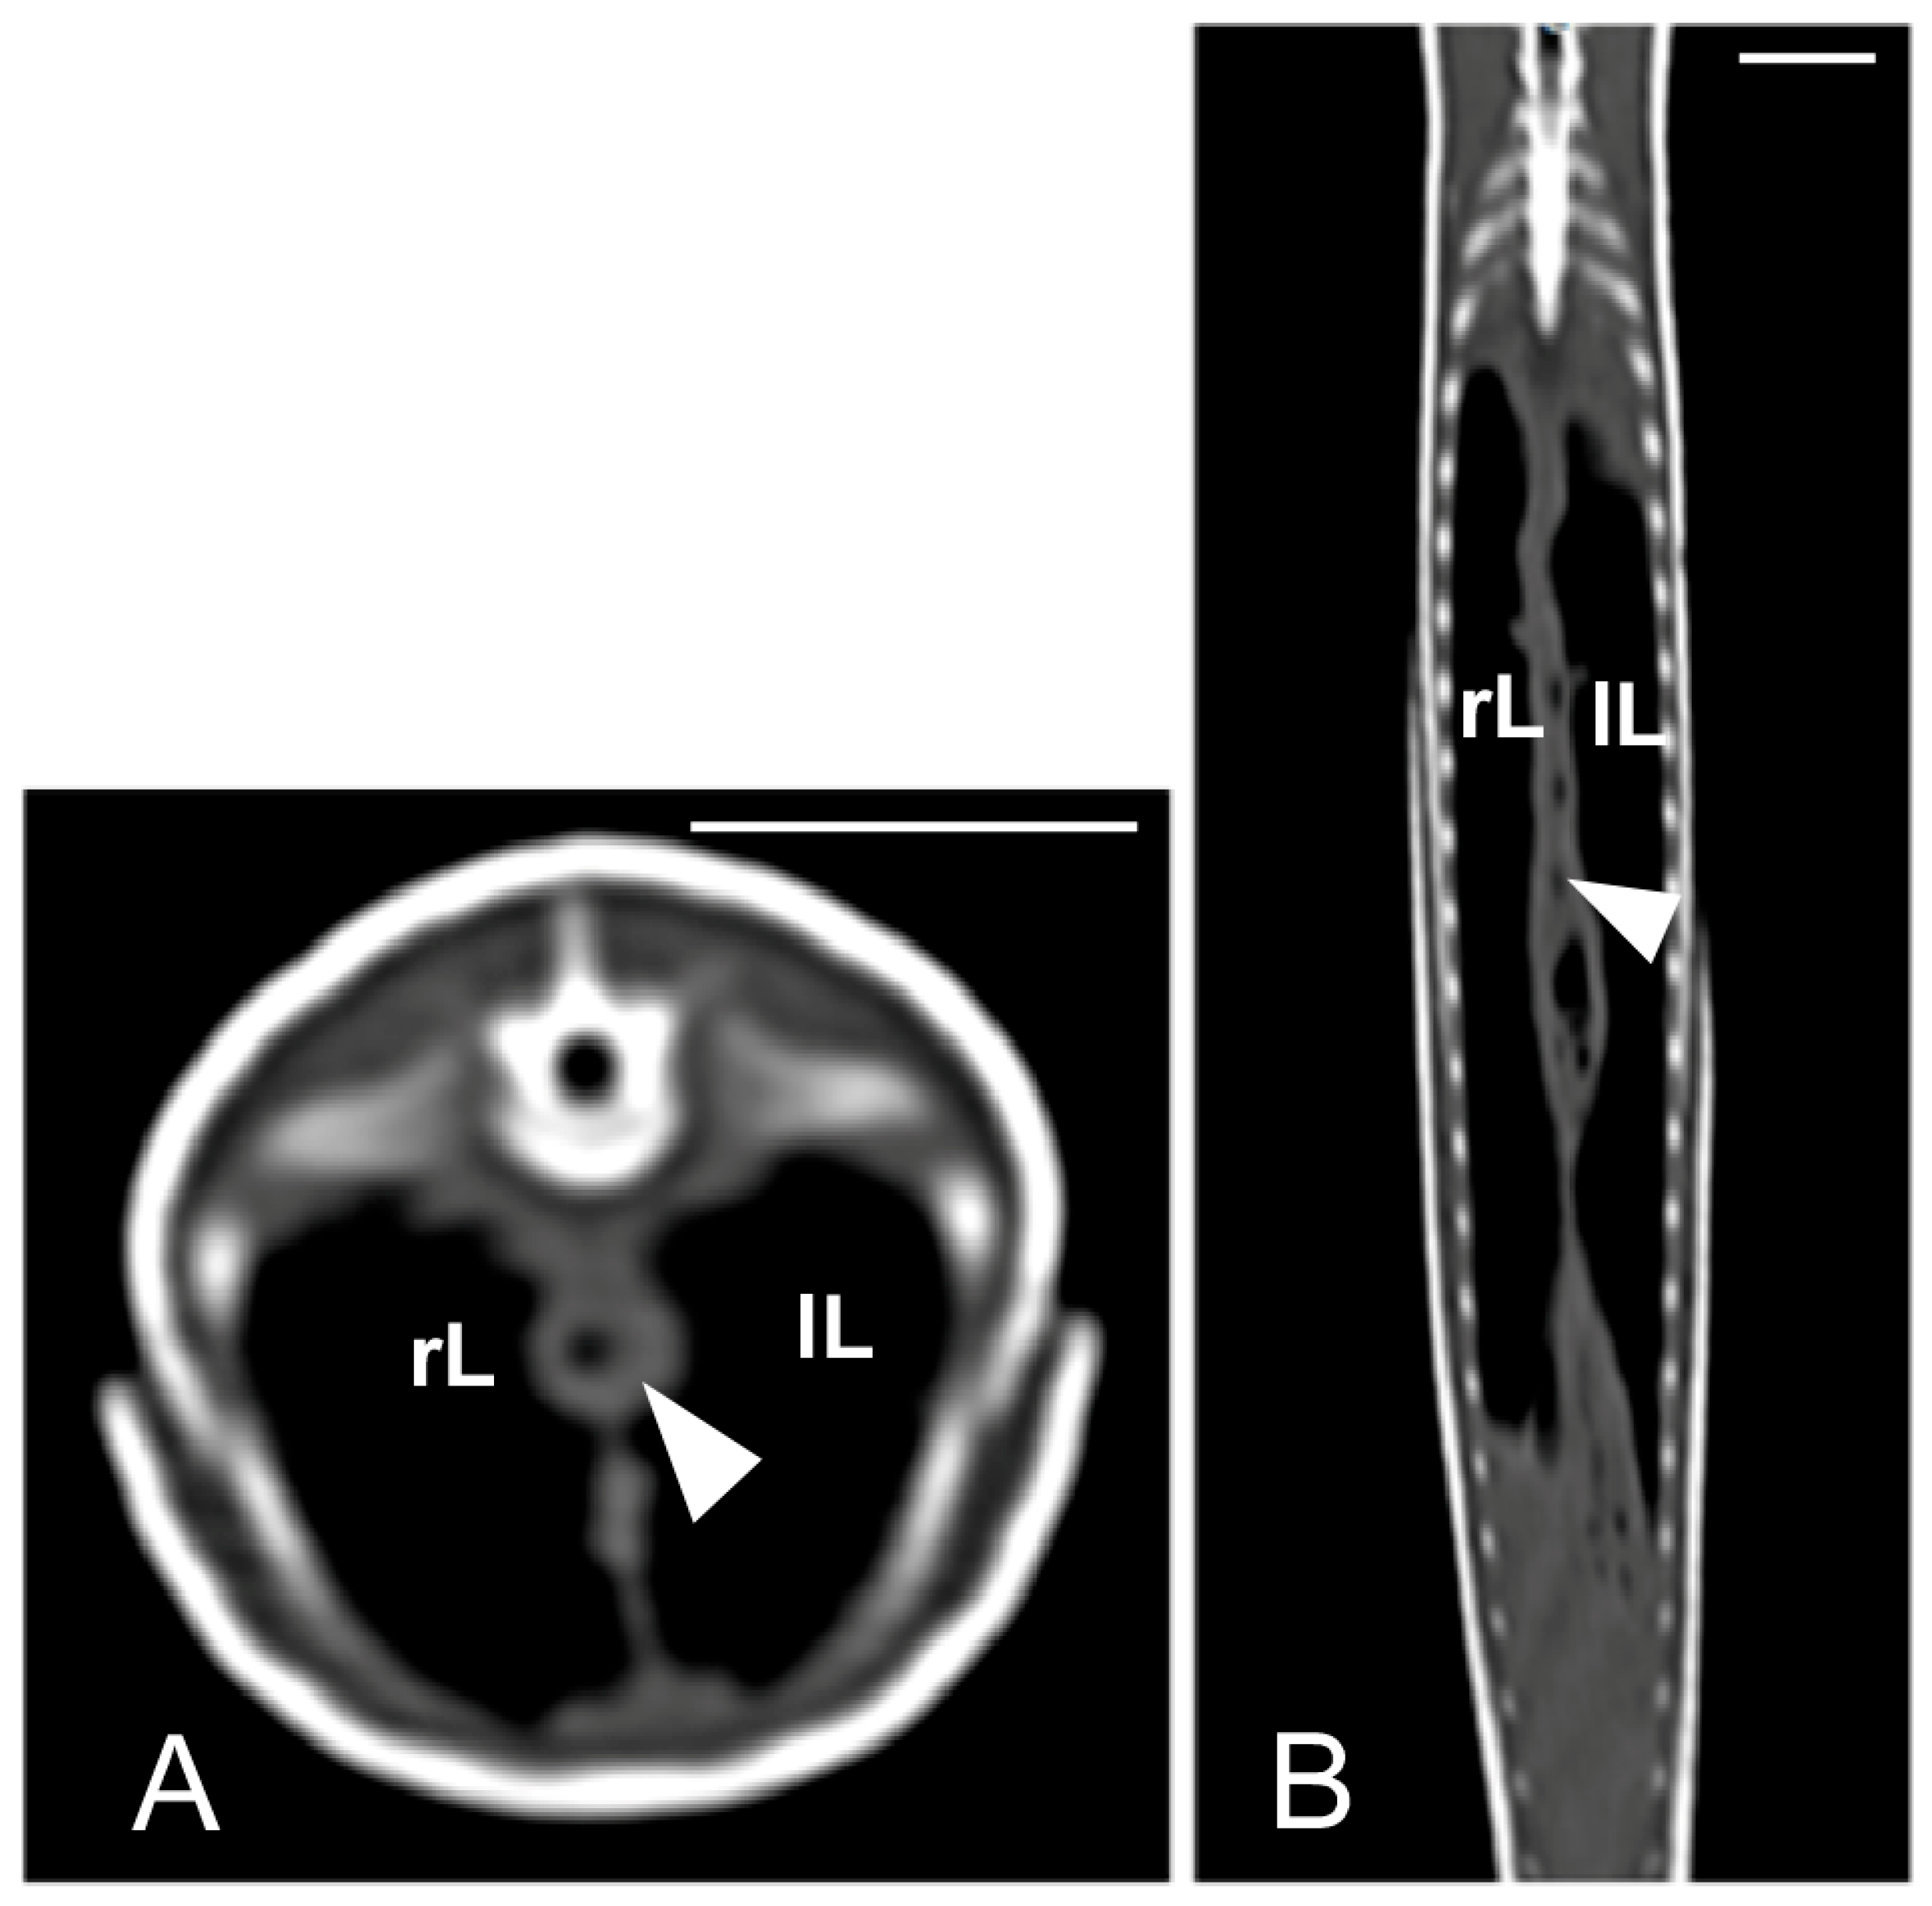

The kidneys and ovaries were identified only in postcontrast CT images. The kidneys appeared as a pair of soft tissue attenuating elongated structures in a ventrolateral position to the spine, in the caudal third of the coelomic cavity. They were best seen in the transverse and dorsal planes. Their margins were not well defined. The aorta was only seen in the midline between them (Figure 13). We could distinguish ovarian follicles only in one individual and they appeared as hypoattenuating rounded to oval structures, bounded by fine slightly hyperattenuating margins (Figure 14). The ureters, urinary bladder, oviducts, testes, and hemipenes were not recognizable in our CT studies.

Figure 13.

The postcontrast CT images of Pseudopus apodus in the dorsal (A) and transverse (B) planes showing both kidneys (white arrows) and the aorta (black arrow) between them in the dorsal part of the coelomic cavity, just ventral to the spine. Bar = 10 mm.

Figure 14.

The postcontrast CT images of Pseudopus apodus in the dorsal (A) and sagittal (B) planes showing ovarian follicles (arrows), just cranial to the kidney. In image A, the aorta (black arrowhead) is identified in the midline. In image B, the white arrowhead points to the right kidney. Bar = 10 mm.